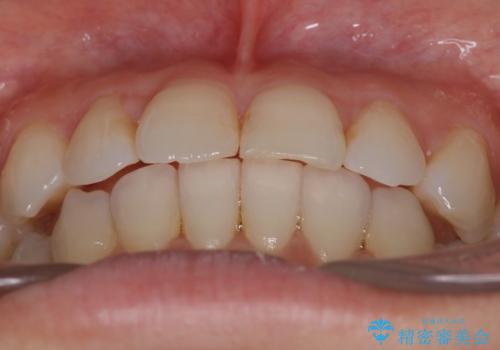

八重歯と前歯のガタガタをインビザラインで

インビザラインで目立たずに治療を終えることができ、喜んでいただけました。

- 八重歯と前歯のガタガタを主訴に来院されました。

目立たず矯正したいとのことでインビザラインで矯正することとしました。